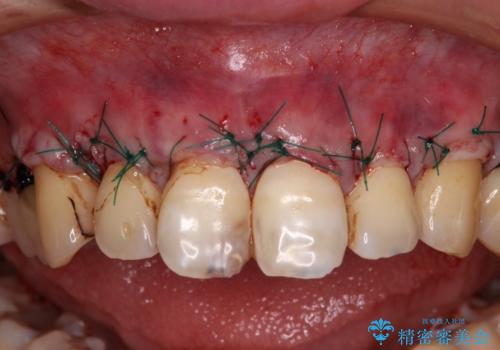

まずは歯肉移植術により顕著に露出している歯根面を被覆して自然な歯肉ラインとし、同時に歯肉の厚みを増大させることで将来の歯肉退縮を予防することを提案しました。

犬歯を中心に、露出量の多かった歯は十分に被覆することができました。

また、歯根のシルエットが見えた術前の状態と比較して、術後は歯肉が非常に厚くなっている状態となりました。